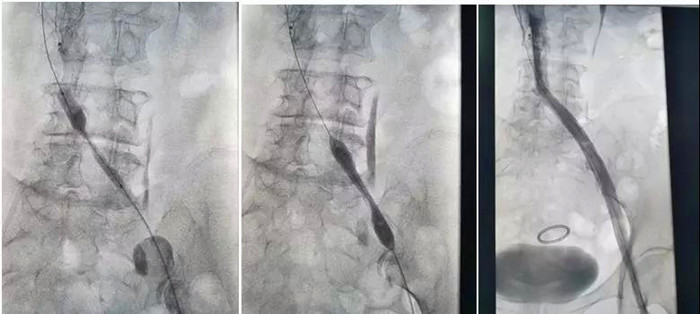

樊奶奶入住后,血管外科團(tuán)隊(duì)在陸煒的帶領(lǐng)下,爭(zhēng)分奪秒為樊奶奶研究病情,量身制定診療方案。第二天下午,陸煒為樊奶奶進(jìn)行了“下腔靜脈濾器置入+吸栓+髂靜脈支架成形術(shù)”。

明確血栓部位后,從腫脹的患肢進(jìn)入AngioJet機(jī)械血栓清除裝置,通過(guò)AngioJet吸栓導(dǎo)管噴射溶栓藥物后對(duì)血栓進(jìn)行抽吸。血栓被一點(diǎn)一點(diǎn)抽吸干凈后,再次造影,發(fā)現(xiàn)樊奶奶果然伴有嚴(yán)重的“髂靜脈壓迫綜合征”,如果不進(jìn)行處理,血栓很容易再次復(fù)發(fā)。陸煒帶領(lǐng)血管外科手術(shù)團(tuán)隊(duì)熟練地進(jìn)行了“髂靜脈球囊擴(kuò)張和支架植入”。

溶栓、抽吸、擴(kuò)張、支架植入,手術(shù)過(guò)程扣人心弦!

一場(chǎng)手術(shù),一箭三雕,一個(gè)半小時(shí)后,樊奶奶腫脹的左腿血液運(yùn)輸終于恢復(fù)了通暢。